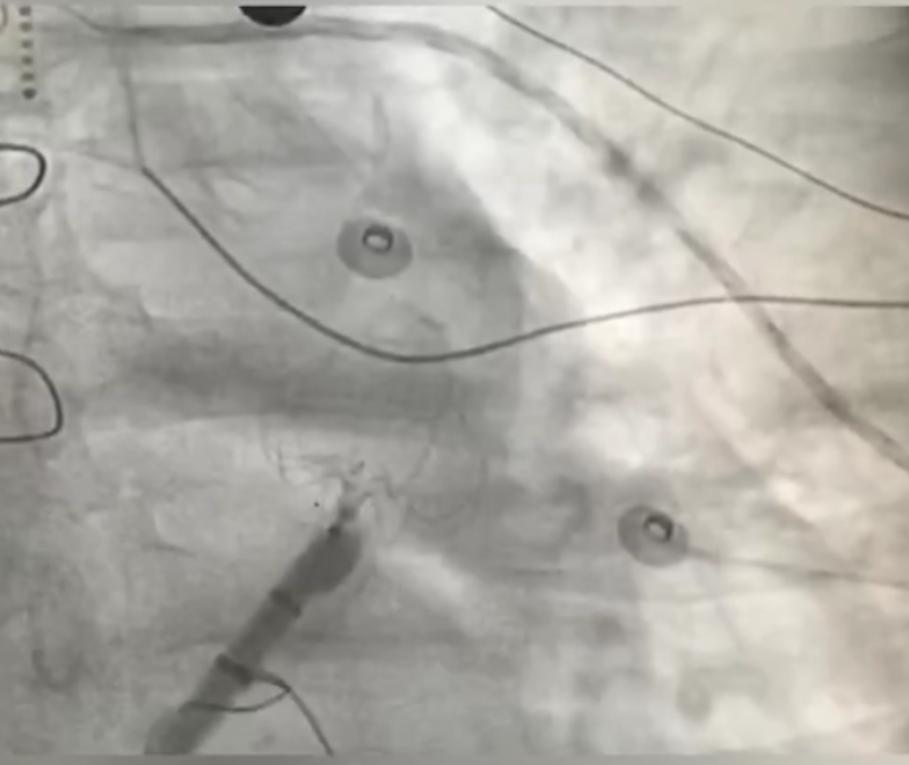

左心耳封堵器的植入

术中ICE指导左心耳封堵器植入